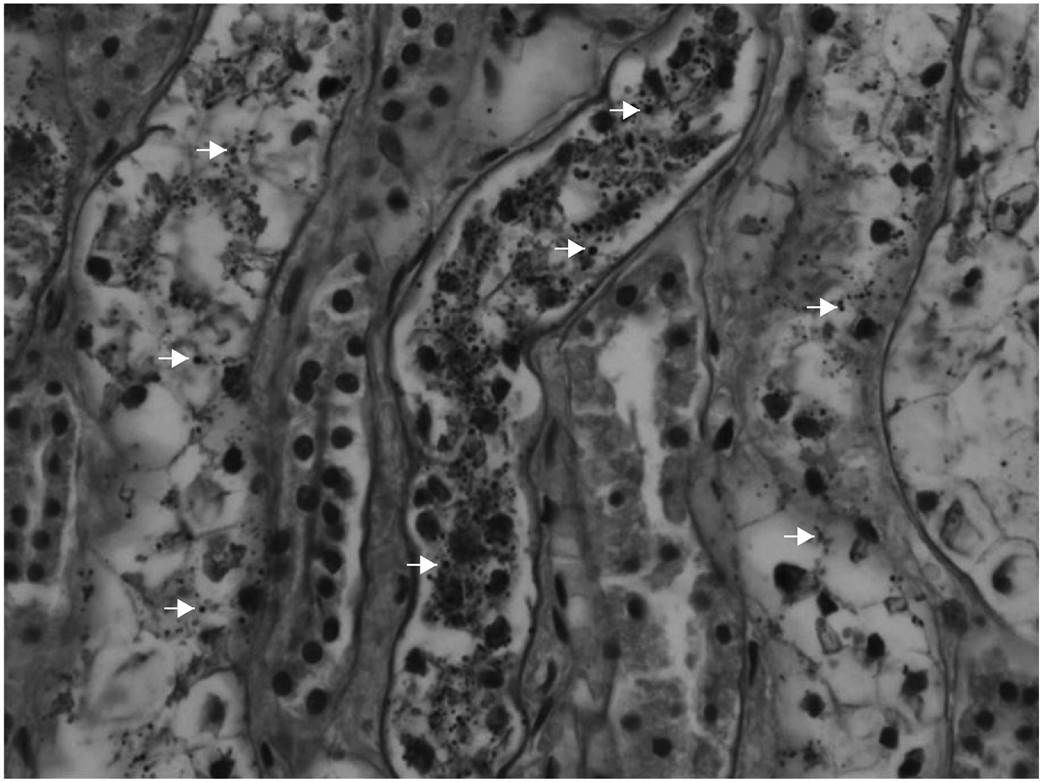

Большая часть молекул глюкозы в клетках человека депонируется в форме высоко разветвленного полимера — гликогена («животного крахмала»). В паренхиме почек в физиологических условиях концентрации этого полисахарида очень низкие, близкие к следовым. Однако при гипергликемии количество гликогена значительно повышается. Морфологически в эпителии проксимальных канальцев обнаруживаются поражения Армани-Эбштейна. Они были впервые описаны Luciano Armanni в 1872 году и характеризуются более светлой цитоплазмой пораженных клеток за счет вакуолизации и накопления гликогена (рис. 1). Гистохимически гликоген обнаруживается с помощью PAS-реакции (Periodic Acid Shiff reaction, синоним – ШИК-реакция). Ее принцип — окисление гликольных групп в молекуле гликогена под воздействием йодной кислоты с образованием альдегидных соединений, легко реагирующих с реактивом Шиффа (фуксин-сернистая кислота) [1].

Гликоген накапливается преимущественно в клетках толстой части восходящего колена петли Генле и дистальных извитых канальцев. Эти компартменты нефрона расположены после проксимальных канальцев и в значительной степени зависят от уровня метаболизма глюкозы как основного источника энергии, которая далее расходуется на работу АТФ-азы для обеспечения процессов реабсорбции. Именно в этом участке наблюдаются поражения Армани-Эбштейна (цитоплазматические включения гликогена), также отмечены случаи скопления гликогена в ядрах единичных клеток. У пациентов с длительным течением сахарного диабета поражению подвергаются также и проксимальные канальцы [2].